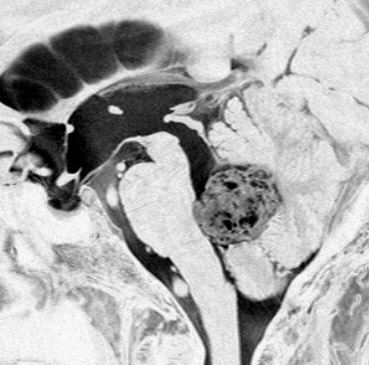

左は脳幹部腫瘍(退形成性神経節膠腫),右は小脳腫瘍(毛様細胞性星細胞腫)です。どちらも第4脳室を埋め尽くすように発育しています。これらはどちら側から発生したかが明瞭な例ですが,第4脳室腫瘍の中には脳幹部からか小脳からか解らないものもあります。でも多くは小脳側からです。脳幹部側からで注意しなければならないのは上衣腫と血管芽腫です。